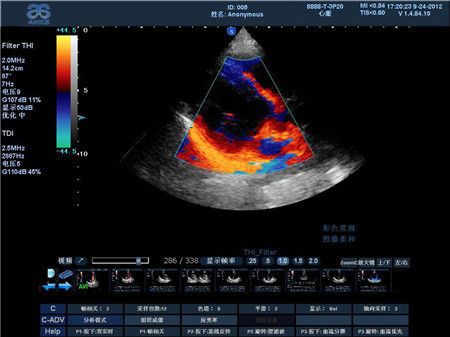

彩色多普勒超声

子宫肌壁内血流信号较非妊娠期丰富,子宫动脉舒张期血流增加,阻力指数RT<0.80;宫腔内蜂窝状液性暗区儿乎无血流信号。卵巢黄素囊肿囊壁间隔可见细条状血流信号,RI为0.40~0.50 。彩色多普勒超声又称B超、彩超,适用于全身各部位脏器超声检查尤其适用于心脏、肢体血管和浅表器官以及腹部、妇产等检查诊断。